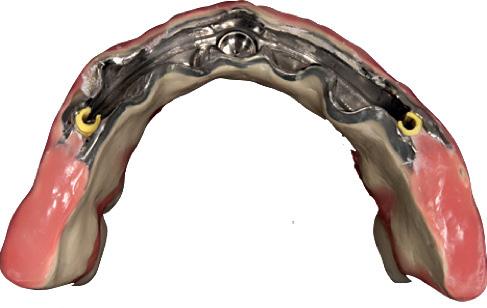

A combination of a rigid metal structure over the telescopic bar and a thimble structure made of PEEK (Fig. 13,14) works as base for the final restorations.

In this case, a patient presented with extremely atrophic bone in the mandible, with four short implants placed between the dental nerve foramen (Fig, 10a,10b). These were milled out of a BRILLIANT Crios disc either as single tooth units or bridges and cemented on the thimble struc-ture (Fig. 15-17). Using BRILLIANT Crios instead of prefabricated teeth, we can increase the strength of the restoration, have good aesthetics and keep the weight low for this kind of prosthesis.

Fig. 17: BRILLIANT Crios restorations used for removable telescopic implant prosthesis.

Fig. 18: Final case in the mouth of the patient. Wearing a complete denture on top and tele-scopic BRILLIANT Crios on the